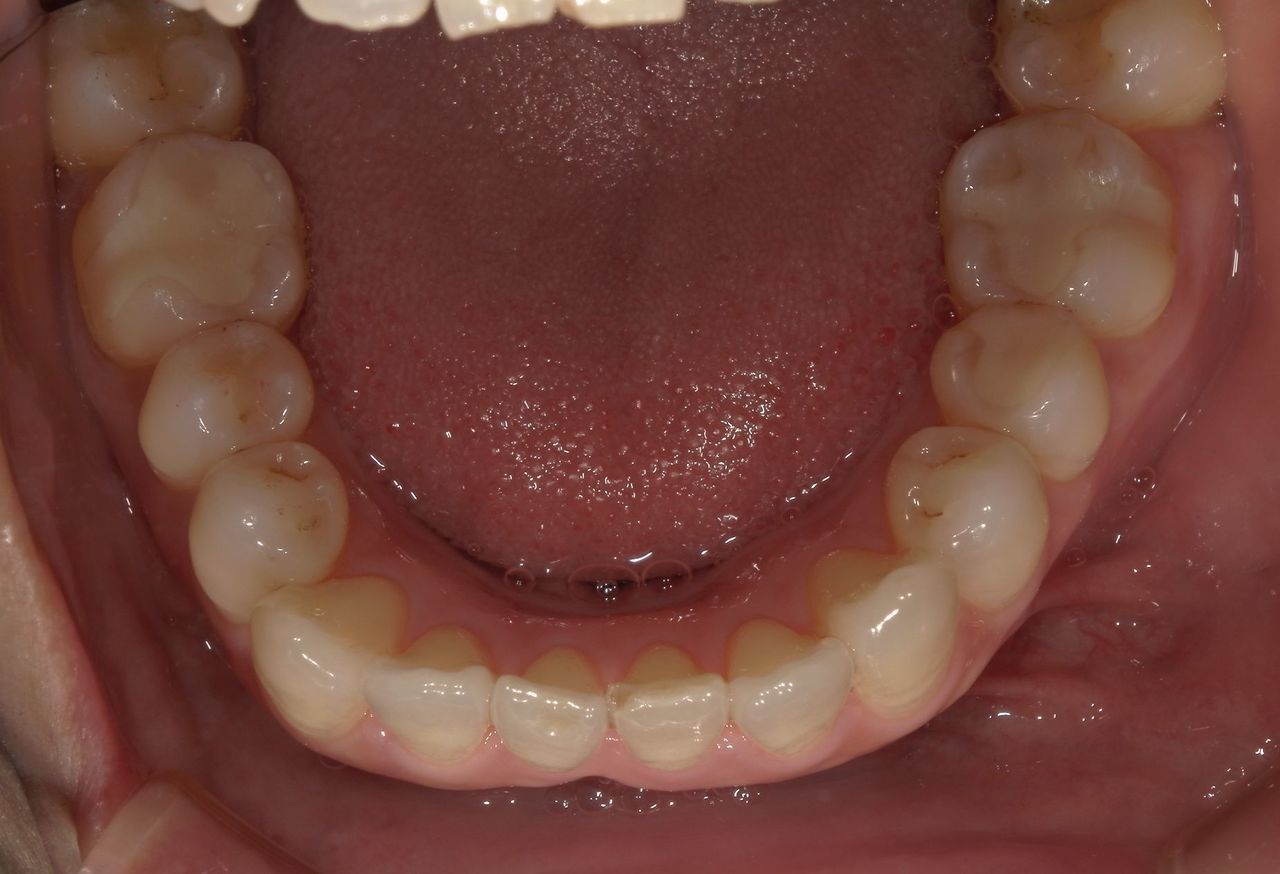

当院ではCADCAM(キャドカム)装置を導入しています。キャドカムとは硬質レジンのブロックから機械で詰め物を削り出す装置です。

銀歯は目立つから嫌だという方には、保険診療で白い詰め物が可能になりました。歯の欠損が大きい場合やブリッジなどは保険適応外になるため、より強度が強いセラミックやジルコニアをお勧めします(自費治療)。

古くなった銀歯は虫歯になりやすく、成分が溶け出してアレルギーの原因になることから、当院では銀歯のやり替えをお勧めしています。

20代・女性

皮膚科で金属アレルギーと診断されて受診しました。他院では銀歯以外は保険治療ではできなくて、それ以外は全て自費のセラミックと言われました。こちらでは保険の白い歯についても詳しく説明していただきました。見た目も自然で、皮膚症状も軽くなってとても満足しています。